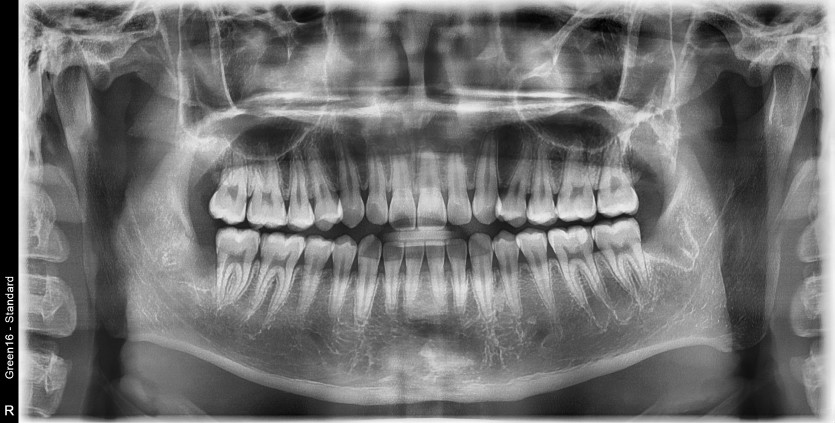

#18,28,38,48 사랑니 발치(#29 과잉치 포함)

구강 외과 전문의가 당일 발치했습니다.